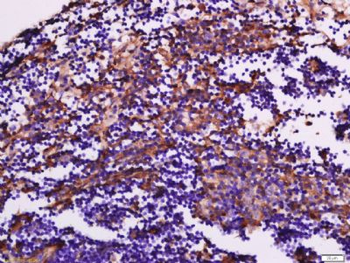

10 μg, 100 μgChemerin Rabbit Polyclonal Antibody [orb156351]

IF, IHC-Fr, IHC-P

Bovine, Porcine

Human, Mouse, Rabbit, Rat

Rabbit

Polyclonal

Unconjugated

100 μl, 200 μl, 50 μlGoat anti-CYP26B1 Antibody [orb19329]